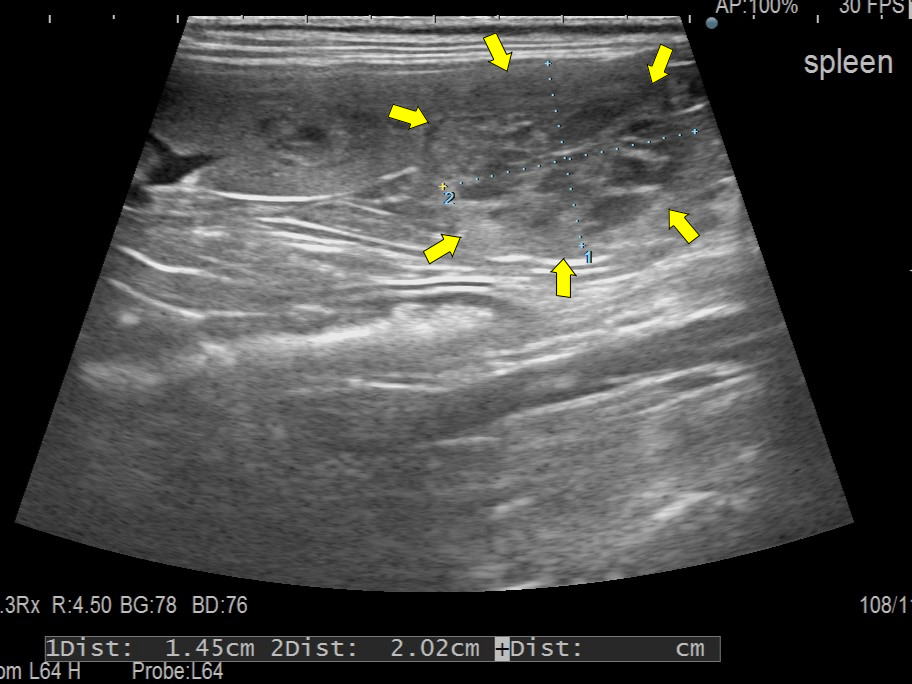

超音波検査画像:脾臓の矢印で囲まれた所に腫瘤が認められた